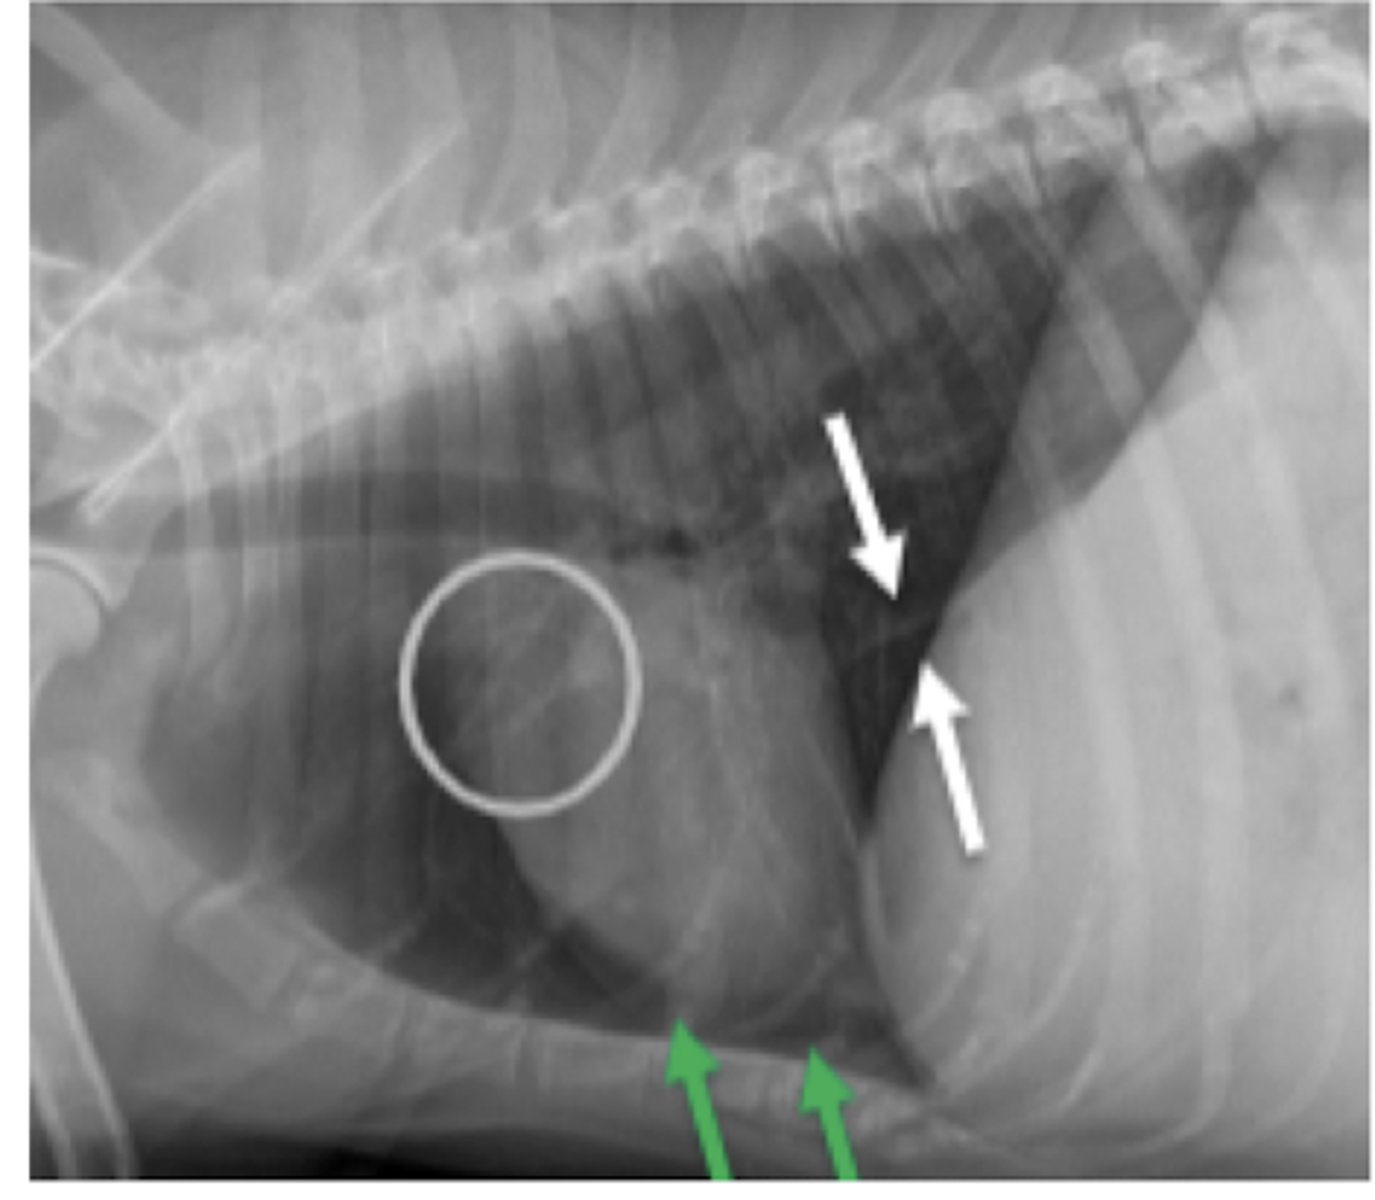

megaesófago

patología:

megaesófago, por cuerpo extraño

neumonía por aspiración por

la parenquíma pulmonar, por riesgo de neumonía por aspiración

si vemos megaesófago en una radiografía, es importante evaluar: